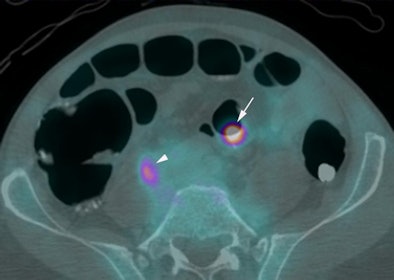

| Above, supine virtual colonoscopy image shows a 20-mm adenoma (arrow) in the sigmoid colon. Below, fused PET/CT in the same patient shows an area of intense F-18 FDG uptake corresponding to the 20-mm adenoma. A small amount of misregistration is present. Arrowhead points to ureteric activity. All images courtesy of Dr. Stuart Taylor. |

Of the 14 polyps that were 6 mm or larger in diameter, 12 (86%, 95% CI: 67%-100%) were avid for F-18 FDG, including all of the lesions 10 mm or larger (mean standardized uptake value [SUV], 10.1), Taylor and his team wrote. Moreover, the group found no significant difference in mean SUV for adenomas with (mean, 12.7) and without (mean, 7.4) high-grade dysplasia (p = 0.10).

CTC's sensitivity for polyps 6 mm or larger of 92.9% (95% CI: 79.4%-100%) did not improve with the addition of PET. However, the combined exam did improve the per-patient positive predictive value for a polyp 10 mm or larger from 73% (95% CI: 39%-92%)to 100% (95% CI: 60%-100%).